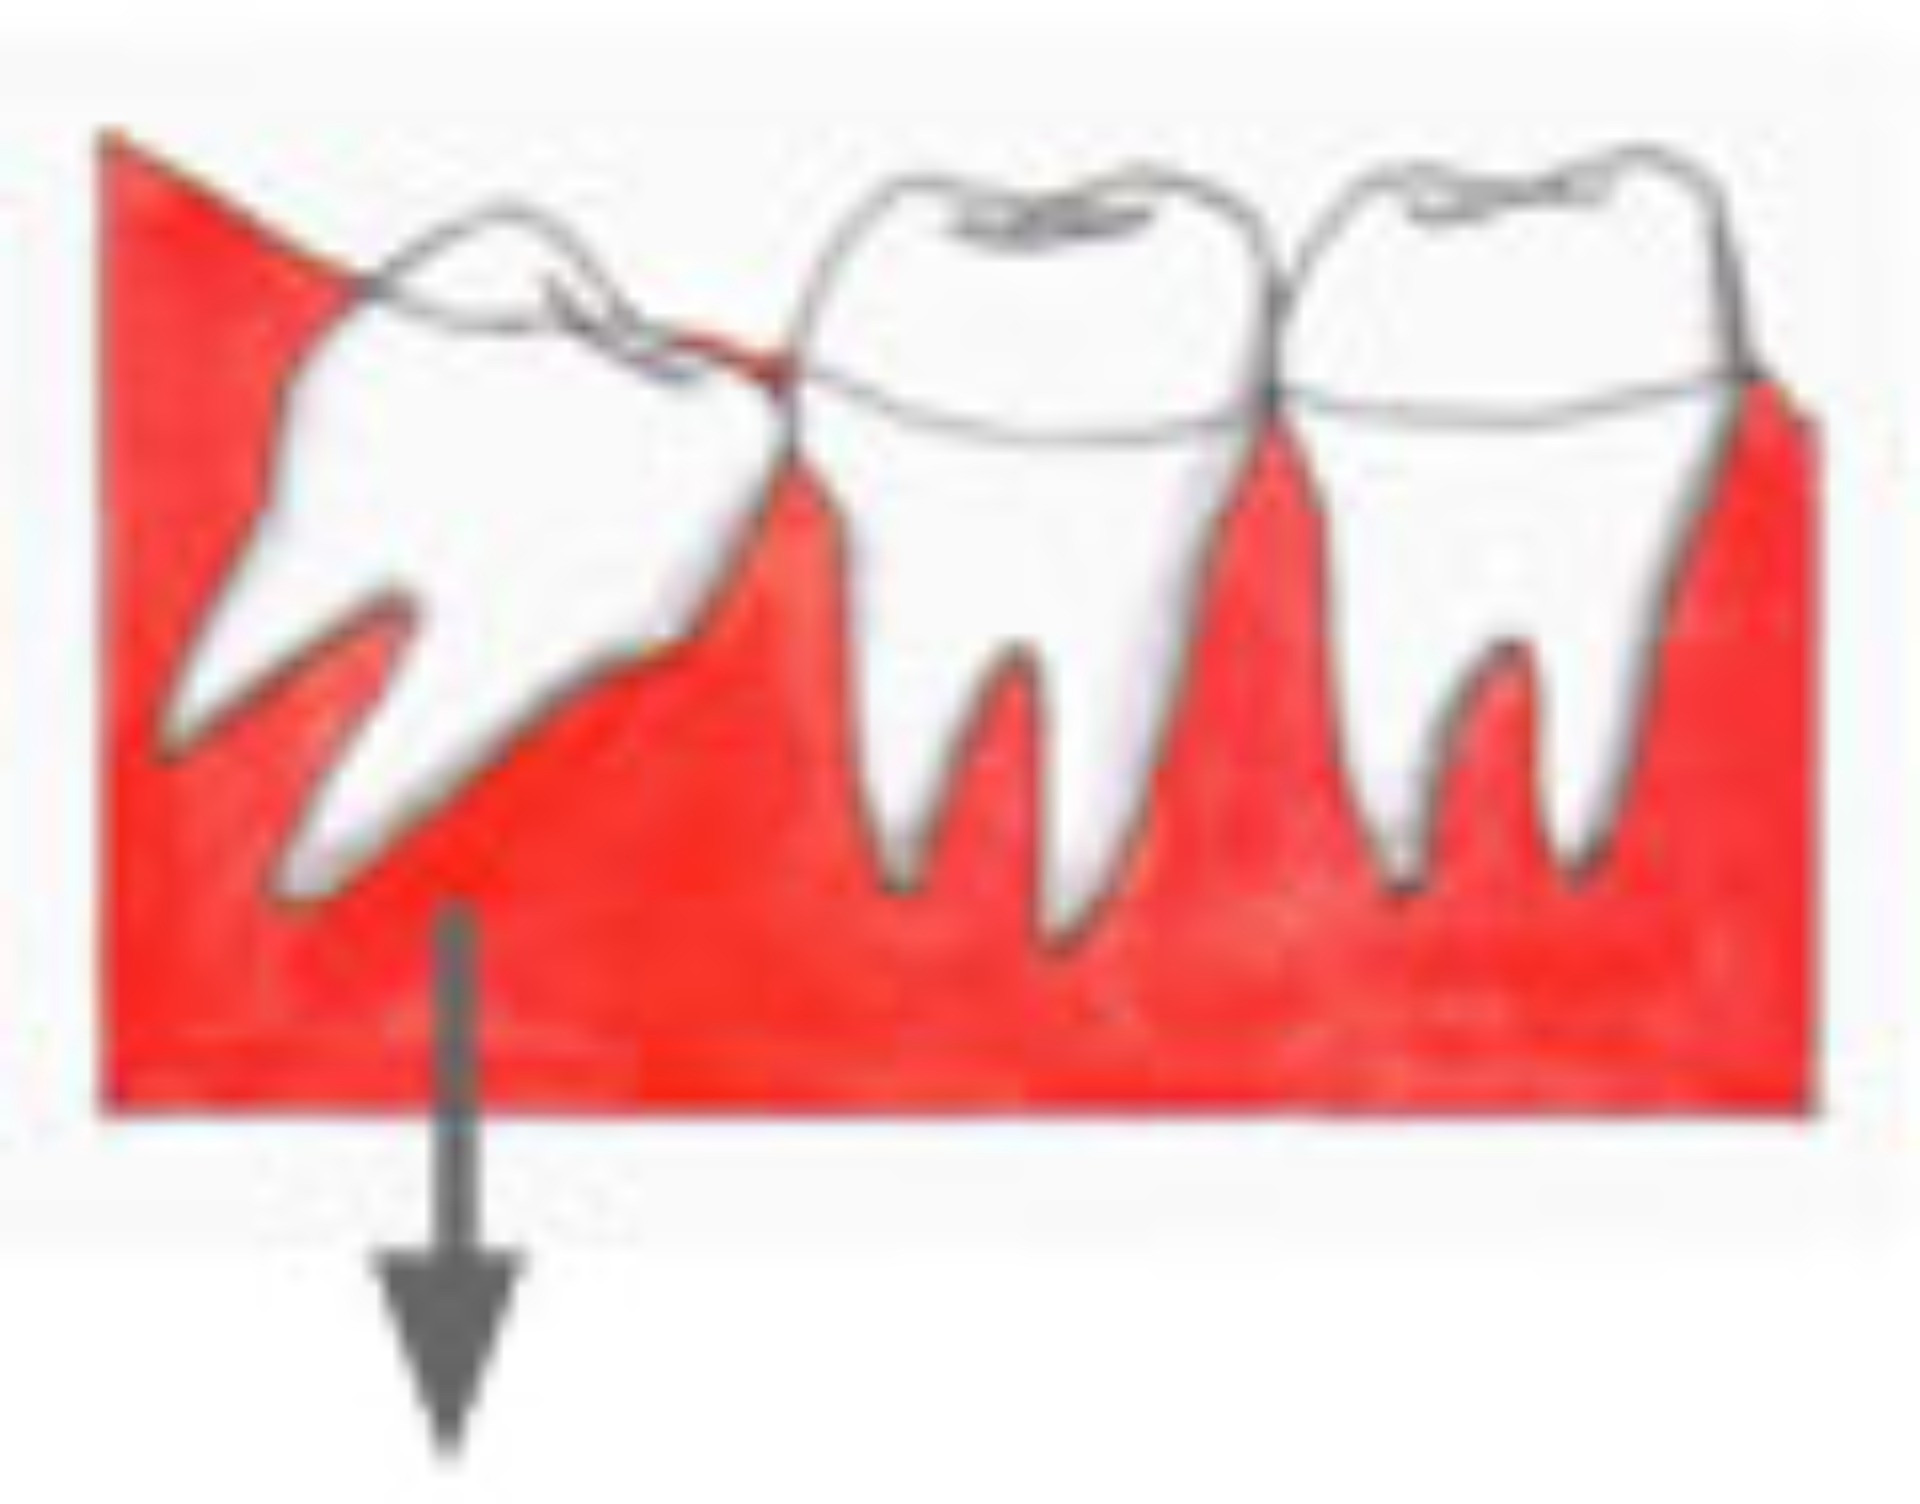

現代の人のアゴの骨は進化して小さくなってきています。しかし、歯の大きさは昔の人とあまり変わってはいません。ですから、最後に出てくる「親知らず」は、出てきたくてもスペースが狭く、正常には出てこない場合が多いのです。 下に挙げる図のように、一部分だけ頭を出しているだけであったり、斜めに傾いて出たり、アゴのなかで水平になったままのこともあります。 |

水平になっている 親知らず |

一部だけ出ている 親知らず |